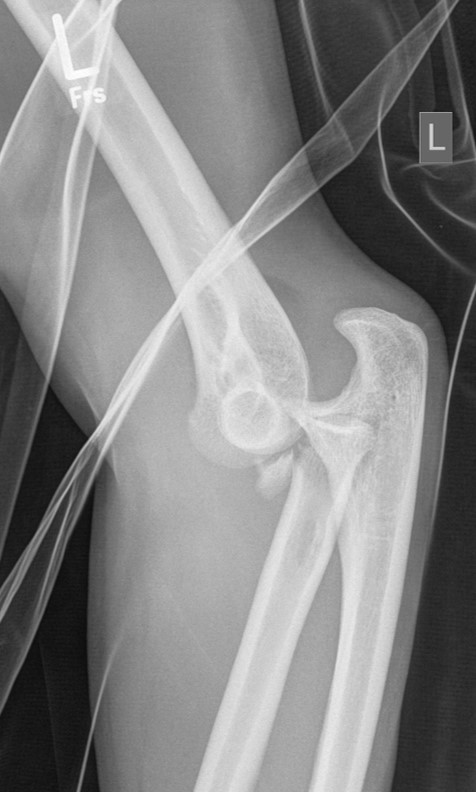

Figure 1: Female patient (36 years) with a Mason type III fracture of the radial head combined with a posterior elbow dislocation. Radiographs on the day of the injury.

Figure 2: Same patient: preoperative CT scans, demonstrating the Mason Type III radial head fracture. No associated bony injuries could be detected.